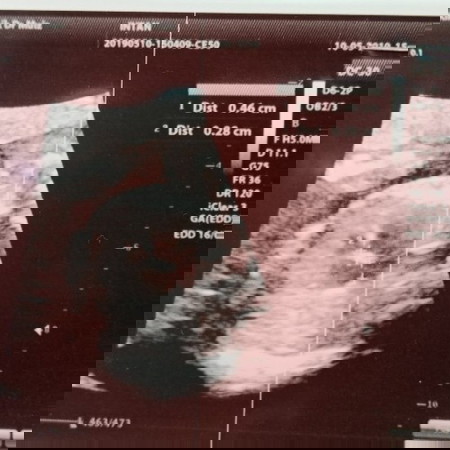

Hi semua.. I just scanned my baby yesterday. Detailed scan. 21w4d. Found out.. Semua benda okay except jantung baby. Ada lubang kecil dekat atas dan bawah. Doktor ada tulis AVSD detected. A kind of heart problem. Ni nak cuba check untuk kali kedua dekat klinik lain. Esok. Hopefully dapat dengar berita gembira. Pray for my baby please.. ?